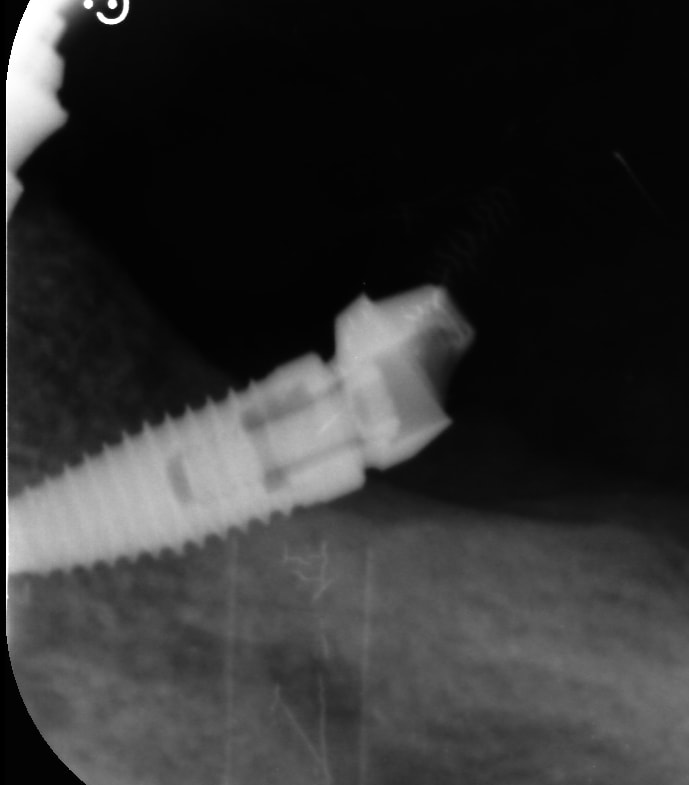

Bah....disons que si l’implant est correctement enfoui ce biseau, tu ne le vois pas.....je dis ça je dis rien....mais je suis sûr que tu suivras le fil conducteur....

pluton écrivait:

" Bah....disons que si l’implant est correctement enfoui ce biseau, tu ne le vois pas.....je dis ça je dis rien..."

je vois ce que tu veux dire , s il etait plus enfouis la gencive ferait joint circulaire , à condition qu il y ait moins d angle aussi je suppose , non ?

ce qui n est quand meme pas logique dans le sens du biseau , bon en meme temps j y connais rien .

Je te rappelle quand même qu’un implant qui est déjà comme ça à ce stade avec une perte osseuse....ça va pas aller en s’arrangeant.....